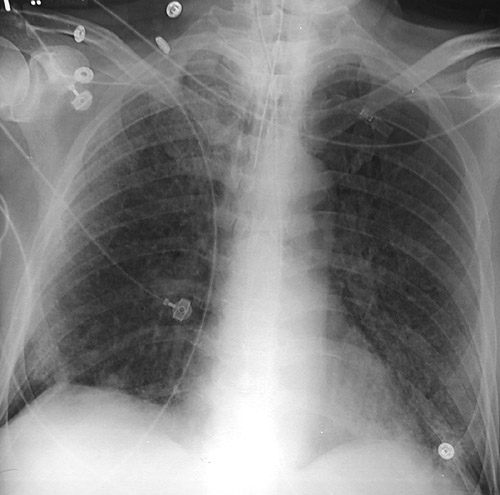

![]() | The portable AP chest radiograph above reveals diffuse small opacifications in all lung fields in a patient who was developing diffuse alveolar damage (DAD) over the past few days. The radiograph below demonstrates the worsening opacifications that are nearly confluent three weeks later at a more advanced stage of DAD. |